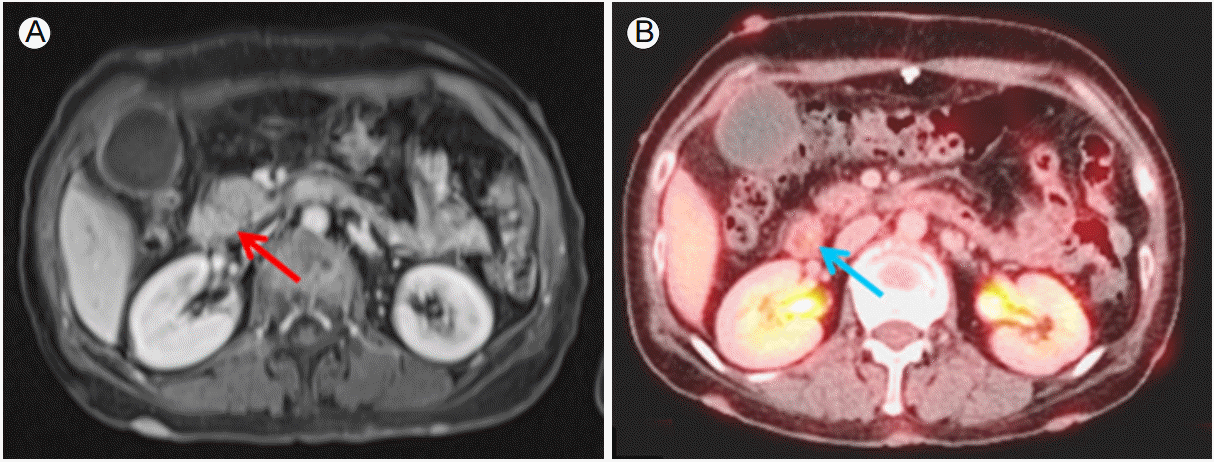

56세에 추적관찰을 위해 시행한 복부 컴퓨터단층촬영상 간내, 간외담관 확장 및 원위부 총담관에 연조직 음영의 종괴가 관찰되었다. 자기공명영상 검사 및 내시경적 초음파 검사를 시행하였으며, 원위부 총담관 침범이 있는 9 × 7 mm 가량의 바터팽대부주위암 의심 소견이 보여 조직검사를 시행하였으나 만성 비특이적 염증 외에 악성세포는 관찰되지 않았다(Fig. 3). 위장관기질종양 재발 가능성이 있다고 판단되어 imatinib (600 mg QD)으로 투여를 시작하였다. 이후 2-3개월 간격으로 종양표지자(CEA, CA 19-9) 및 복부 전산화단층촬영 검사로 추적관찰하였으며, 재발의 악화 소견은 없었다.

(A) Liver MRI (T1 image) shows the ~0.7 cm periampullary mass (arrow). (B) PET-CT shows the mild hypermetabolic lesion in the distal common bile duct, suggesting ampulla of Vater cancer (arrow). MRI, magnetic resonance imaging; PET-CT, positron emission tomography-computed tomography.